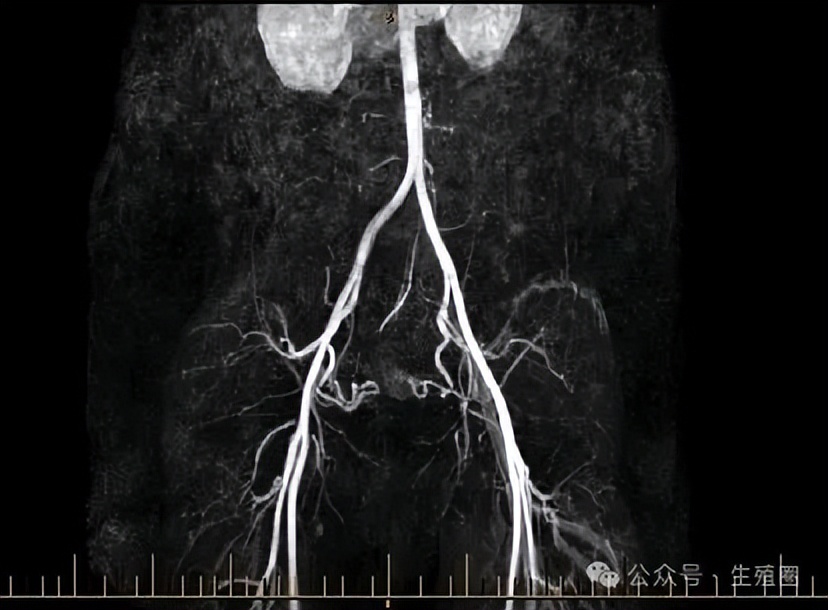

为了看清这团血管的真面目和它的势力范围,医生安排她做了CT血管造影。

这个检查就像给子宫的血管系统拍了一张高清三维地图,放射科的医生看了之后,确认了这是子宫动静脉畸形。

当然,增强CT或核磁共振血管成像能清晰显示畸形血管团的位置、大小、范围以及它和周围血管的关系,对于制定治疗方案至关重要。